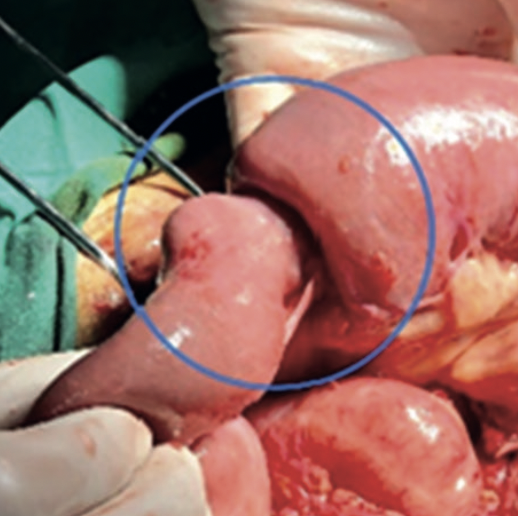

Caso Clínico: Paciente masculino de 39 años de edad con intususcepción aguda que se presentó luego de cirugía por ruptura diafragmática y se encuentra en tratamiento postoperatorio el día 7. El paciente presenta cuadro clínico de obstrucción de intestino delgado. La imagen de tomografía computarizada muestra evidencia de intususcepción yeyuno-yeyunal. Se realizó laparotomía exploradora y resección del intestino necrótico. Los casos raros, como la invaginación intestinal, deben observarse en el posoperatorio y en manifestaciones similares con un examen cuidadoso de los hallazgos característicos de la TC, debido a la detección temprana y la intervención quirúrgica. con reducción manual puede evitar la necesidad de una resección del intestino delgado y posibles complicaciones no deseadas.